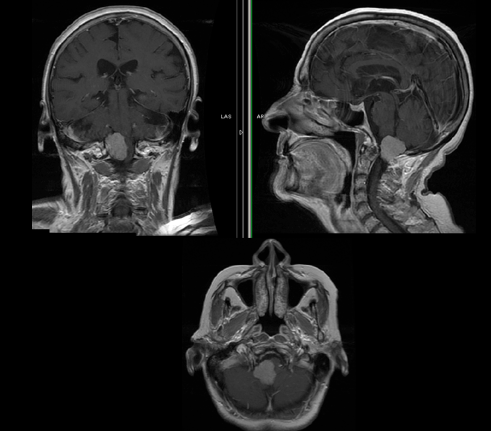

法国一位53岁男性,因三叉神经痛合并三叉神经感觉减退,在当地 神经外科医院 Lariboisiere医院,查出 左侧较大岩斜脑膜瘤 (27立方厘米)。脑磁共振(mri)显示从幕部可见明显的轴外肿...